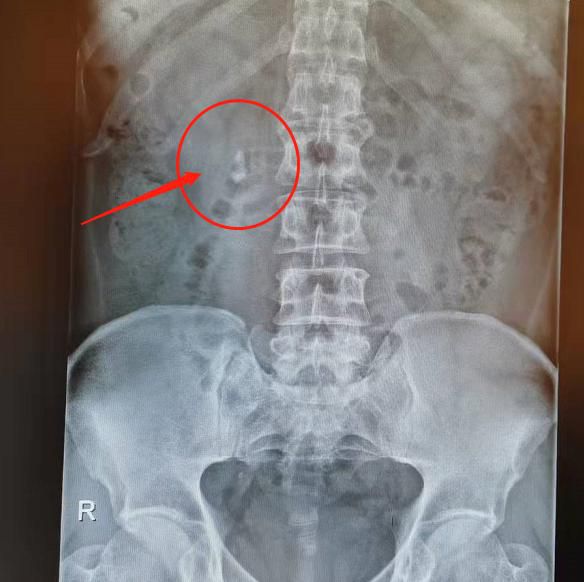

△體外碎石前。